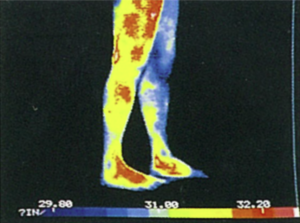

リンパを流す前のサーモグラフィー画像

リンパを流した後のサーモグラフィー画像